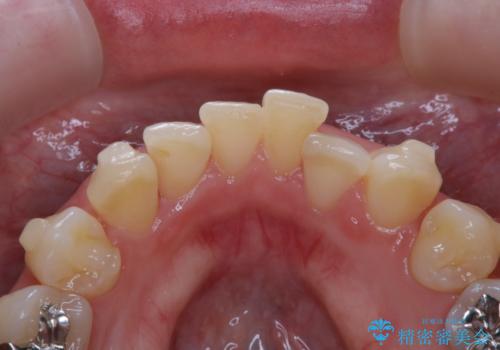

- インビザラインで矯正治療中にクリーニングを希望されました。PMTC60分コースで、クリーニングと歯ブラシ指導を行いました。

磨けているようでも、染出しをして目に見えるプラーク(歯垢)を確認することで、より正しいブラッシング方法を身につけることができます。インビザライン中は、歯にアタッチメントをつけるため、歯の表面がデコボコしてプラークが付きやすい状態になります。毎日のケアでしっかりと汚れを落として虫歯や歯周病・口臭のリスクを減らしていくことが大切です。定期的にメンテナンスを行い、ケアがどれくらい出来ているか確認したり歯科医院で専門的な機械や器具によるPMTCを行うことをおススメします。